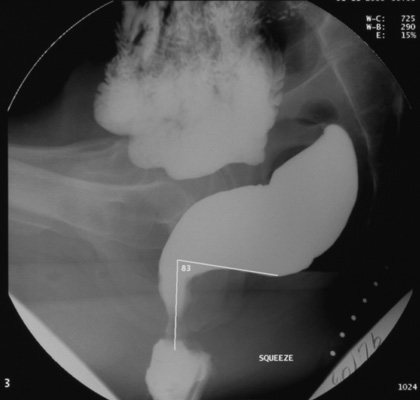

with maximal voluntary contraction of

the sphincter and pelvic floor muscles ("squeeze")

Videofluorography is also done while

the patient performs the following maneuvers: resting state, squeezing and finally, rectal evacuation. In the latter phase of the

study, key events can also be recorded with intermittent digital imaging.